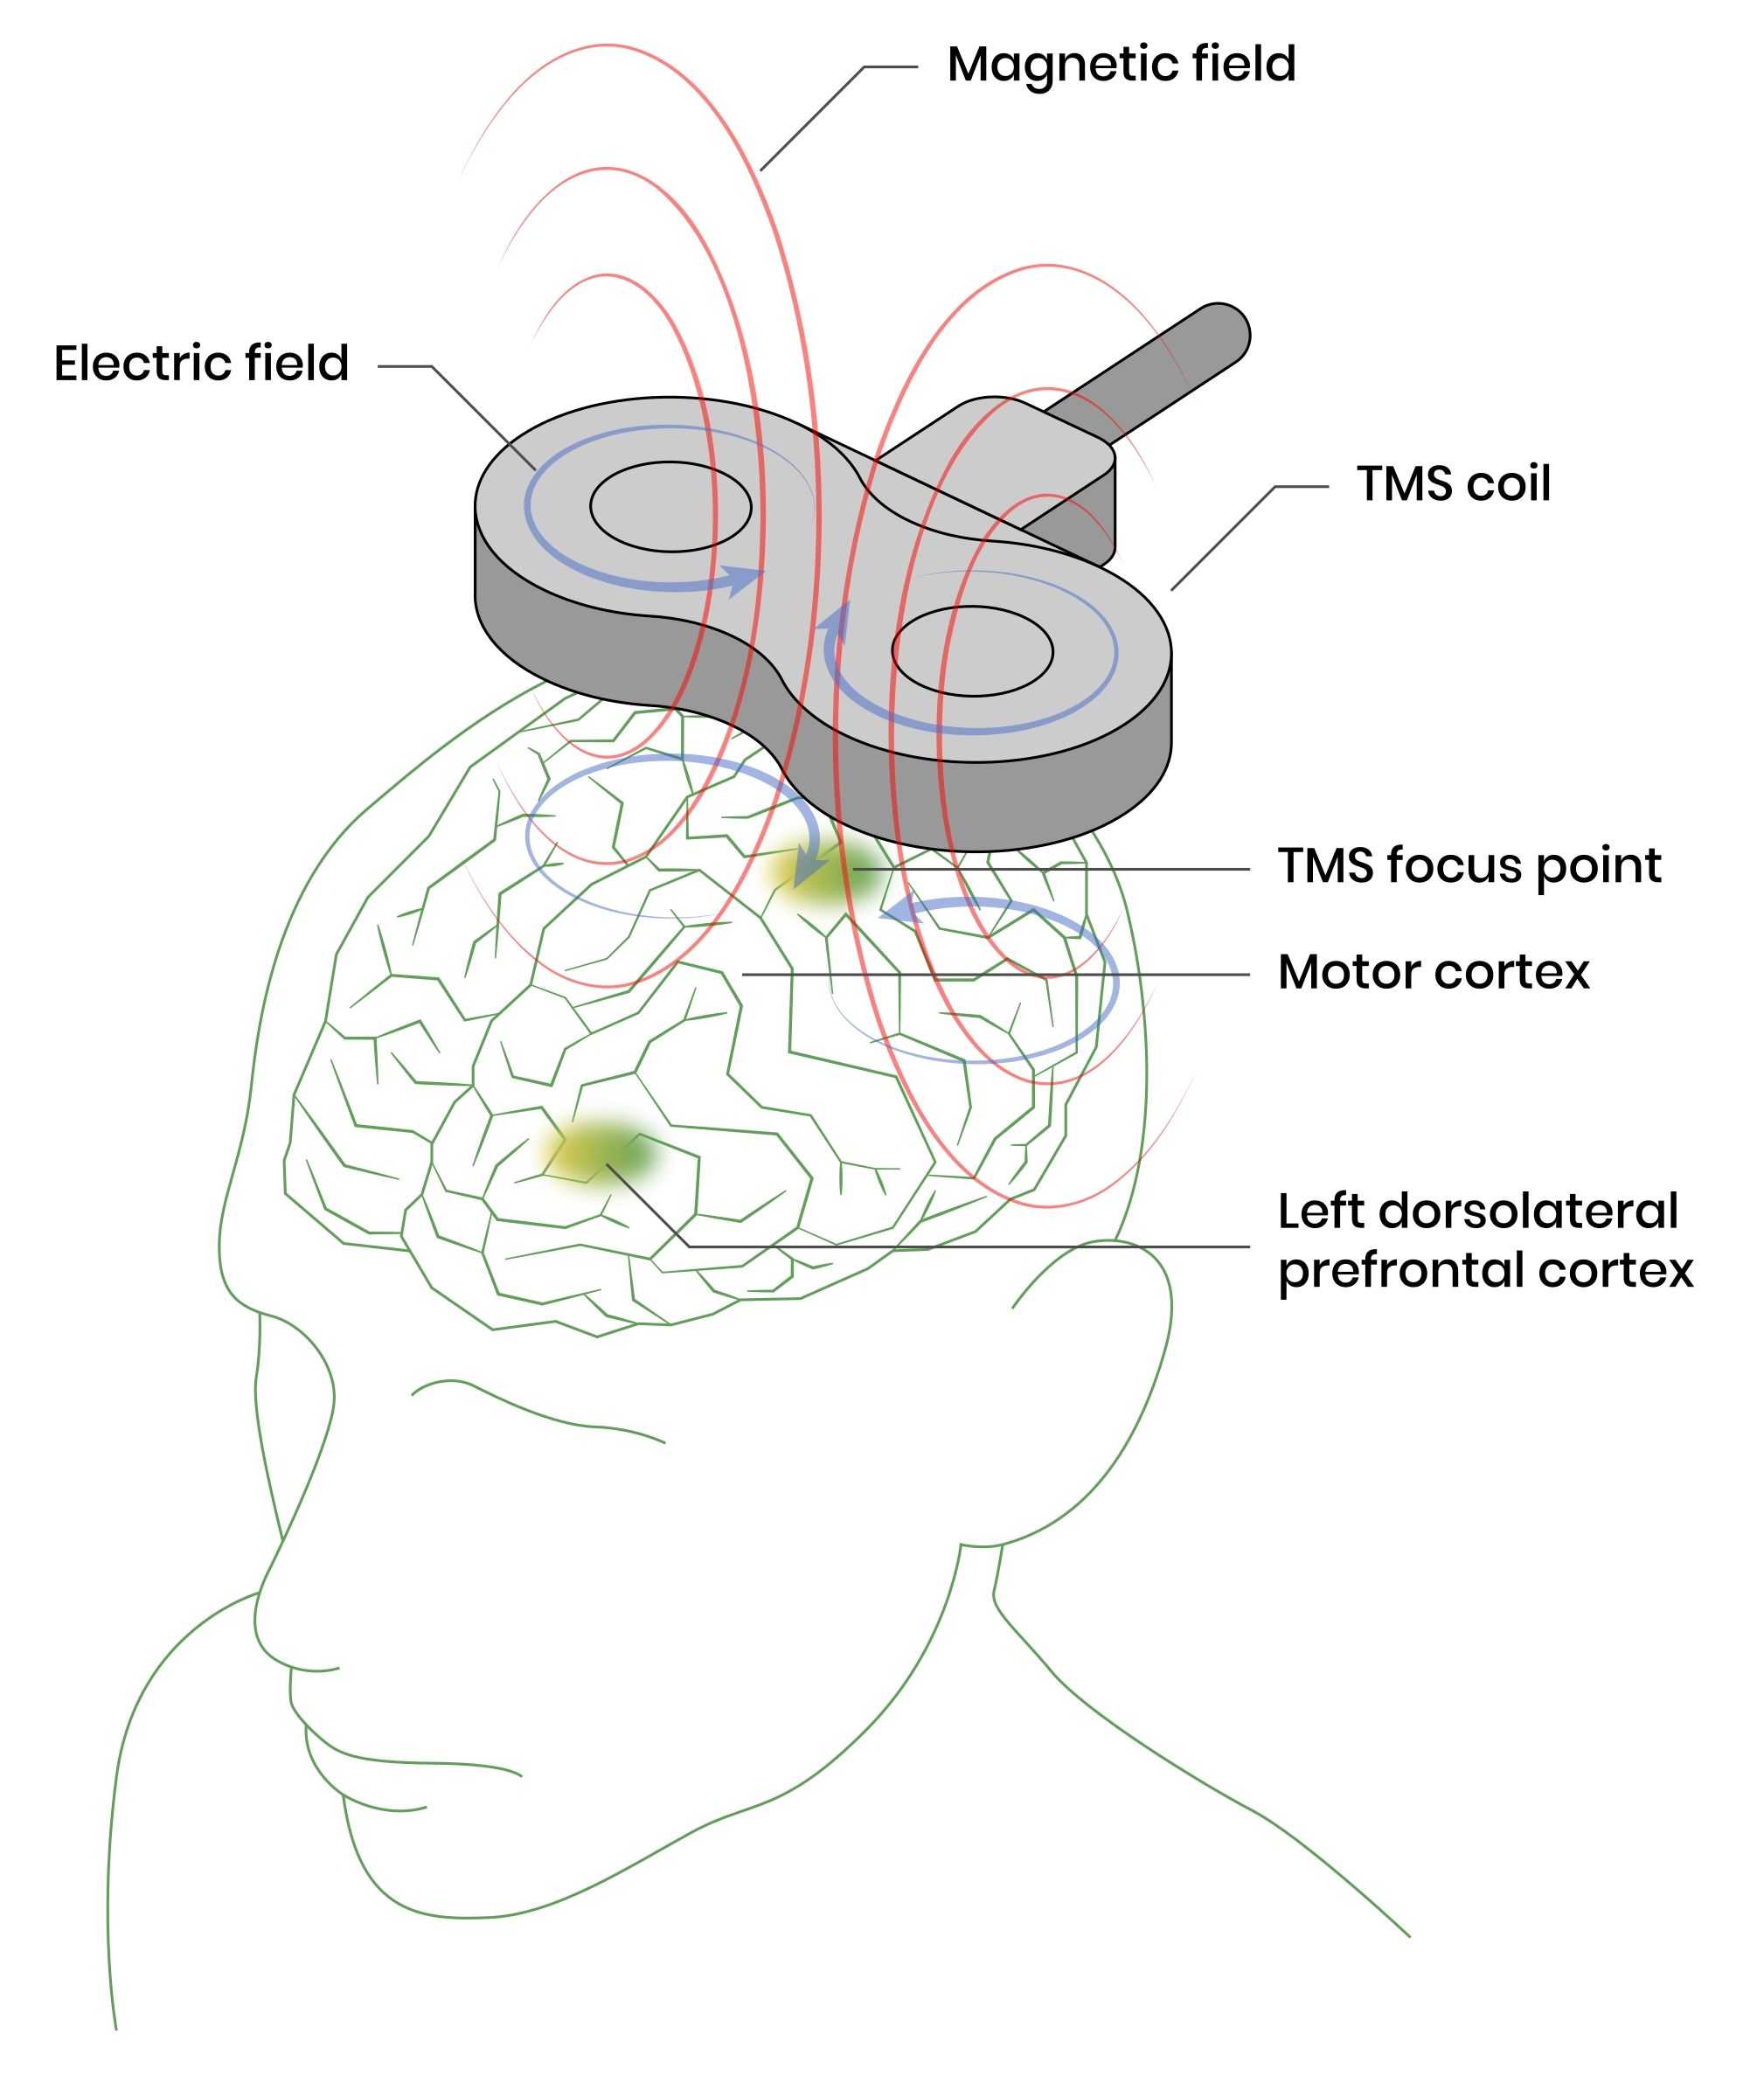

TMS does not require surgery or medication; it works externally by using magnetic stimulation to target specific areas of the brain. It is a non-invasive and well-tolerated method.

TMS can be used to target specific brain regions, such as the prefrontal cortex, without affecting the entire body.